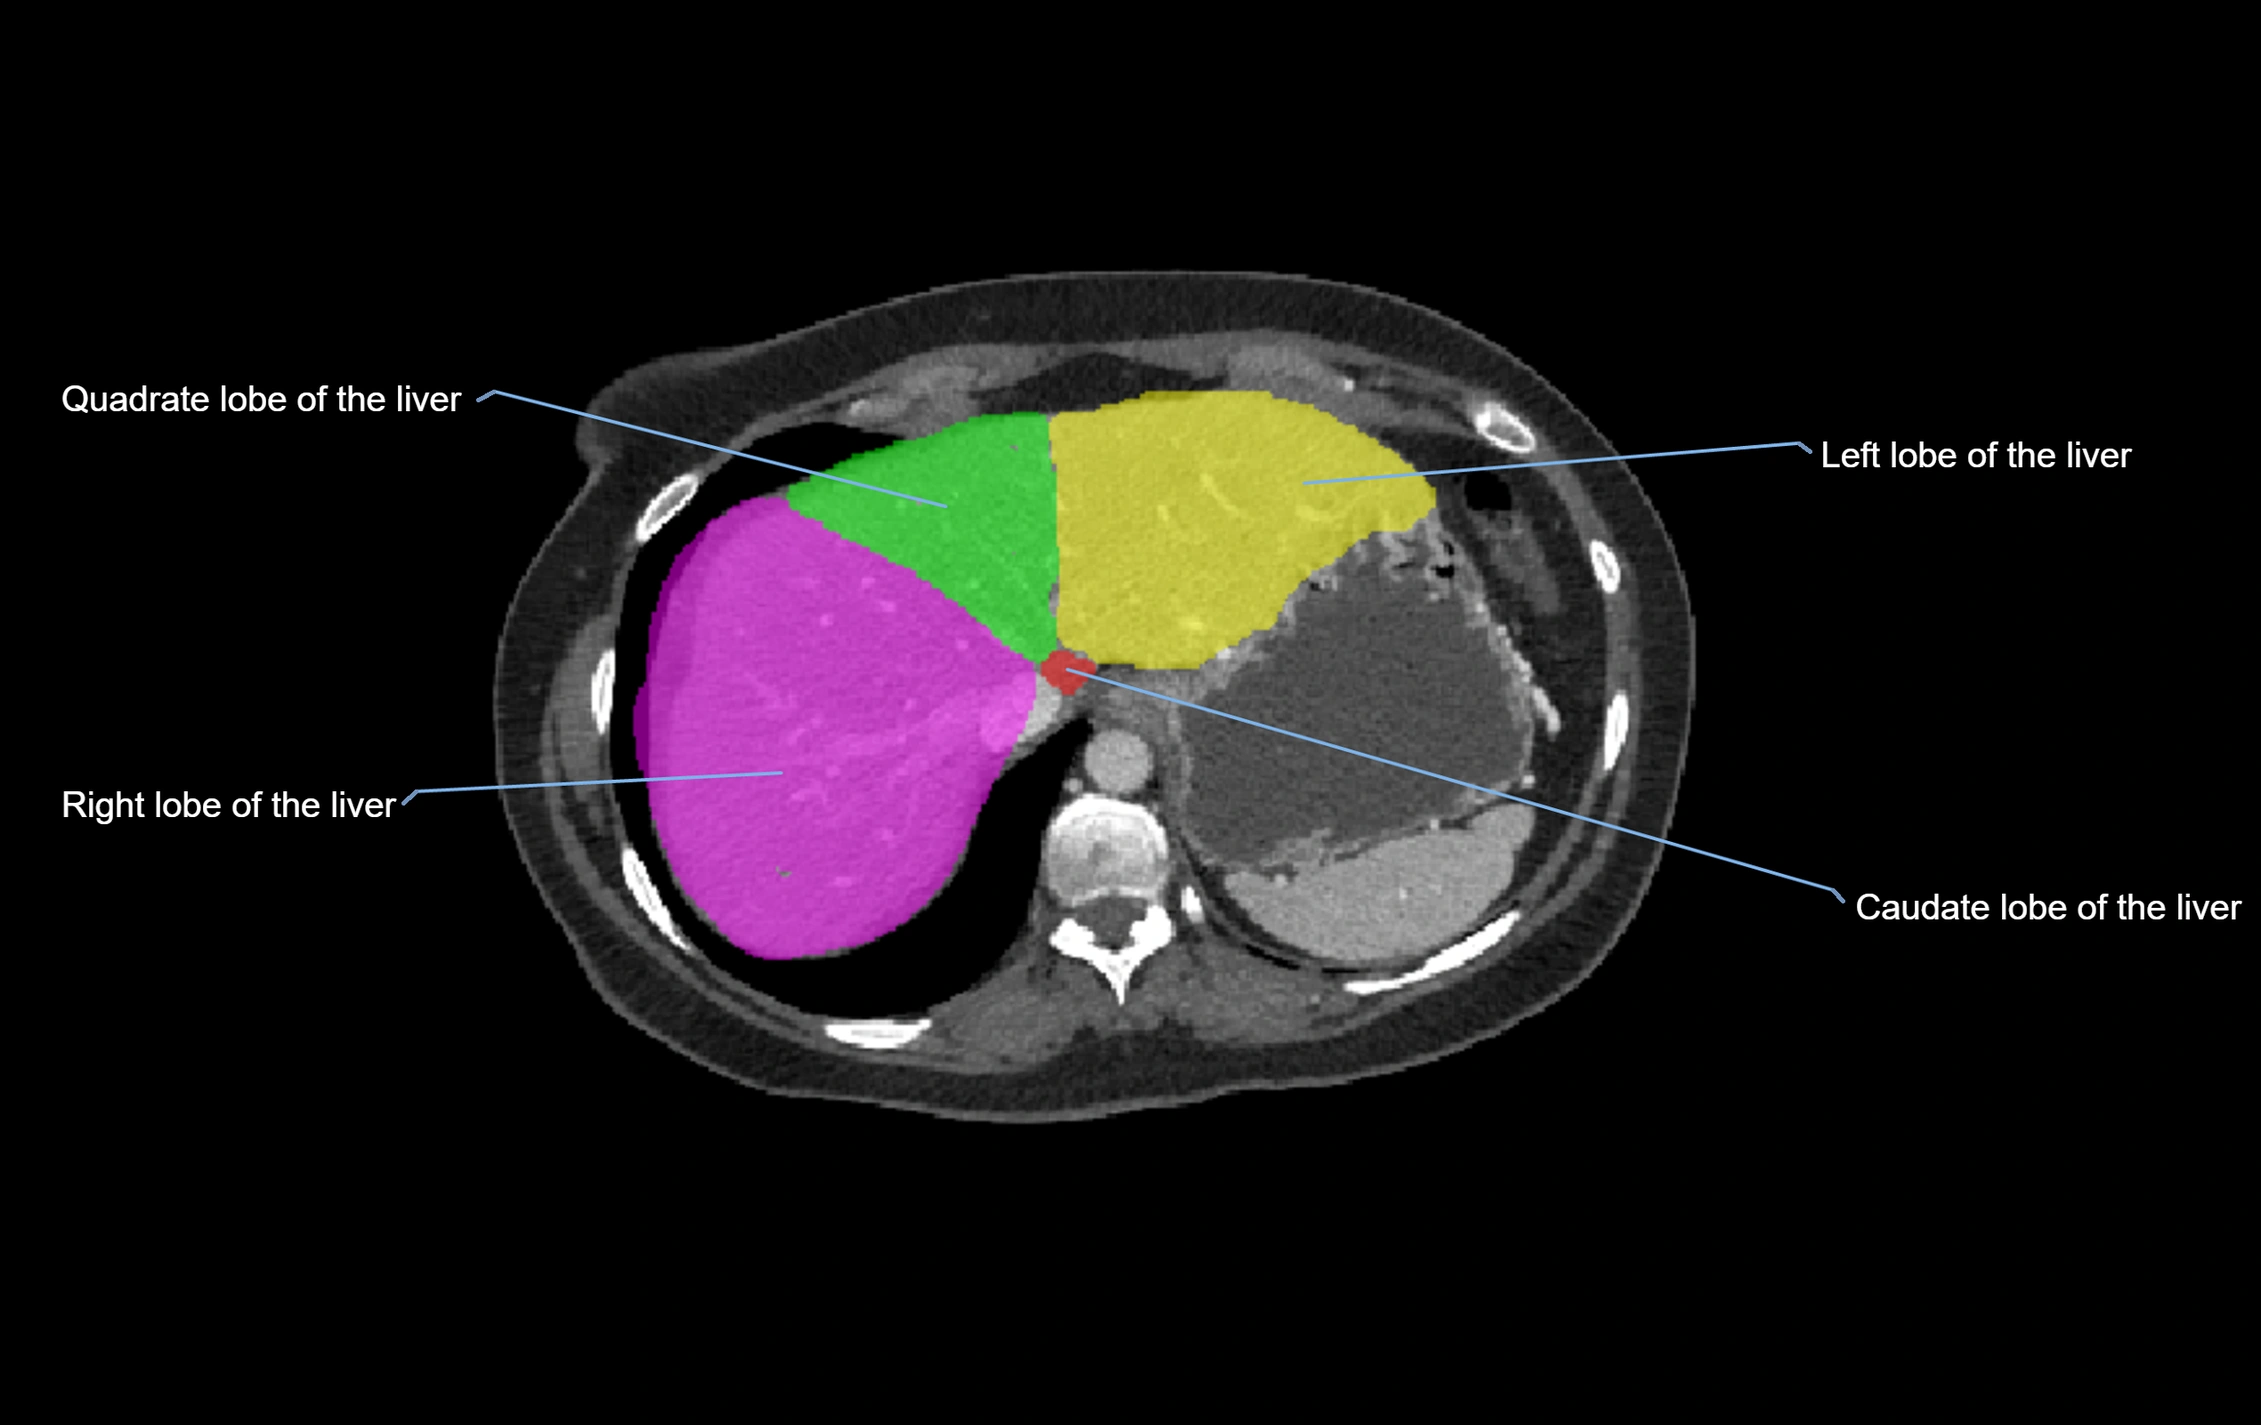

The caudate lobe of the liver is a distinct anatomical subdivision of the liver, designated as segment I in Couinaud’s classification. It lies on the posterior surface of the liver, between the fissure for the ligamentum venosum (left boundary) and the groove for the inferior vena cava (IVC) (right boundary). Superiorly, it is related to the posterior liver surface, and inferiorly it is separated from the left lobe by the porta hepatis.

The caudate lobe is unique because it receives dual portal venous and arterial inflow from both the right and left portal veins and hepatic arteries. It also has independent venous drainage directly into the IVC via multiple small hepatic veins, unlike other lobes that drain through the three main hepatic veins.

CT Image

image